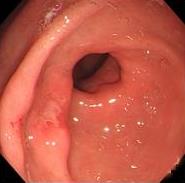

• 色素内镜和窄带成像技术联合放大内镜对早期结直肠癌及癌前病变的诊断价值研究

摘要:目的 探究色素内镜(CE)和窄带成像技术(NBI)联合放大内镜(ME)对早期结直肠癌及癌前病变的诊断价值研究。方法 选取2023年8月-2024年7月于该院接受检查的疑似早期结直肠癌及癌前病变的患者160例。采用四格表法,分析NBI-ME和CE-ME检测早期结直肠癌及癌前病变的敏感度、特异度和准确度;采用Kappa一致性检验,分析CE-ME和NBI-ME诊断早期结直肠癌及癌前病变与病理检查的一致性。结果 病理结果显示,良性病变52例,癌前病变90例,结直肠癌18例。CE-ME检测结果显示,良性病变43例,癌前病变101例,结直肠癌16例,漏诊率为33.33%;CE-ME诊断早期结直肠癌及癌前病变与病理检查的一致性中度(Kappa = 0.605,P < 0.01),敏感度为66.67%,特异度为97.18%,准确度为93.75%。NBI-ME检查结果显示,良性病变43例,癌前病变100例,结直肠癌17例,漏诊率为16.67%,NBI-ME诊断早期结直肠癌及癌前病变与病理检查的一致性较高(Kappa = 0.714,P < 0.01),敏感度为88.33%,特异度为98.59%,准确度为96.88%。CE-ME与NBI-ME两者联合检查结果显示,良性病变56例,癌前病变86例,结直肠癌18例,漏诊率为5.56%,两者联合诊断早期结直肠癌及癌前病变与病理检查的一致性极高(Kappa = 0.857,P < 0.01),敏感度为94.44%,特异度为99.30%,准确度为98.75%,高于CE-ME和NBI-ME单独检查。结论 CE和NBI联合ME对早期结直肠癌及癌前病变具有较高的诊断价值。值得应用于临床。